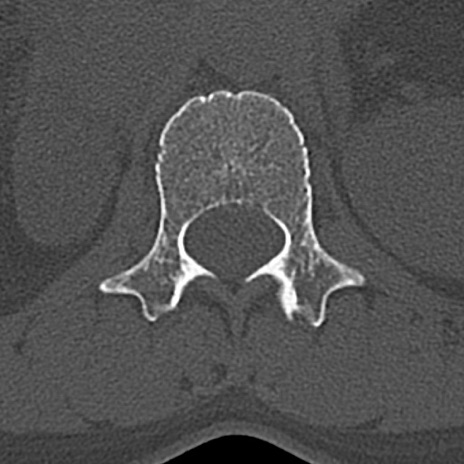

腰椎CT

横断像と矢状断像